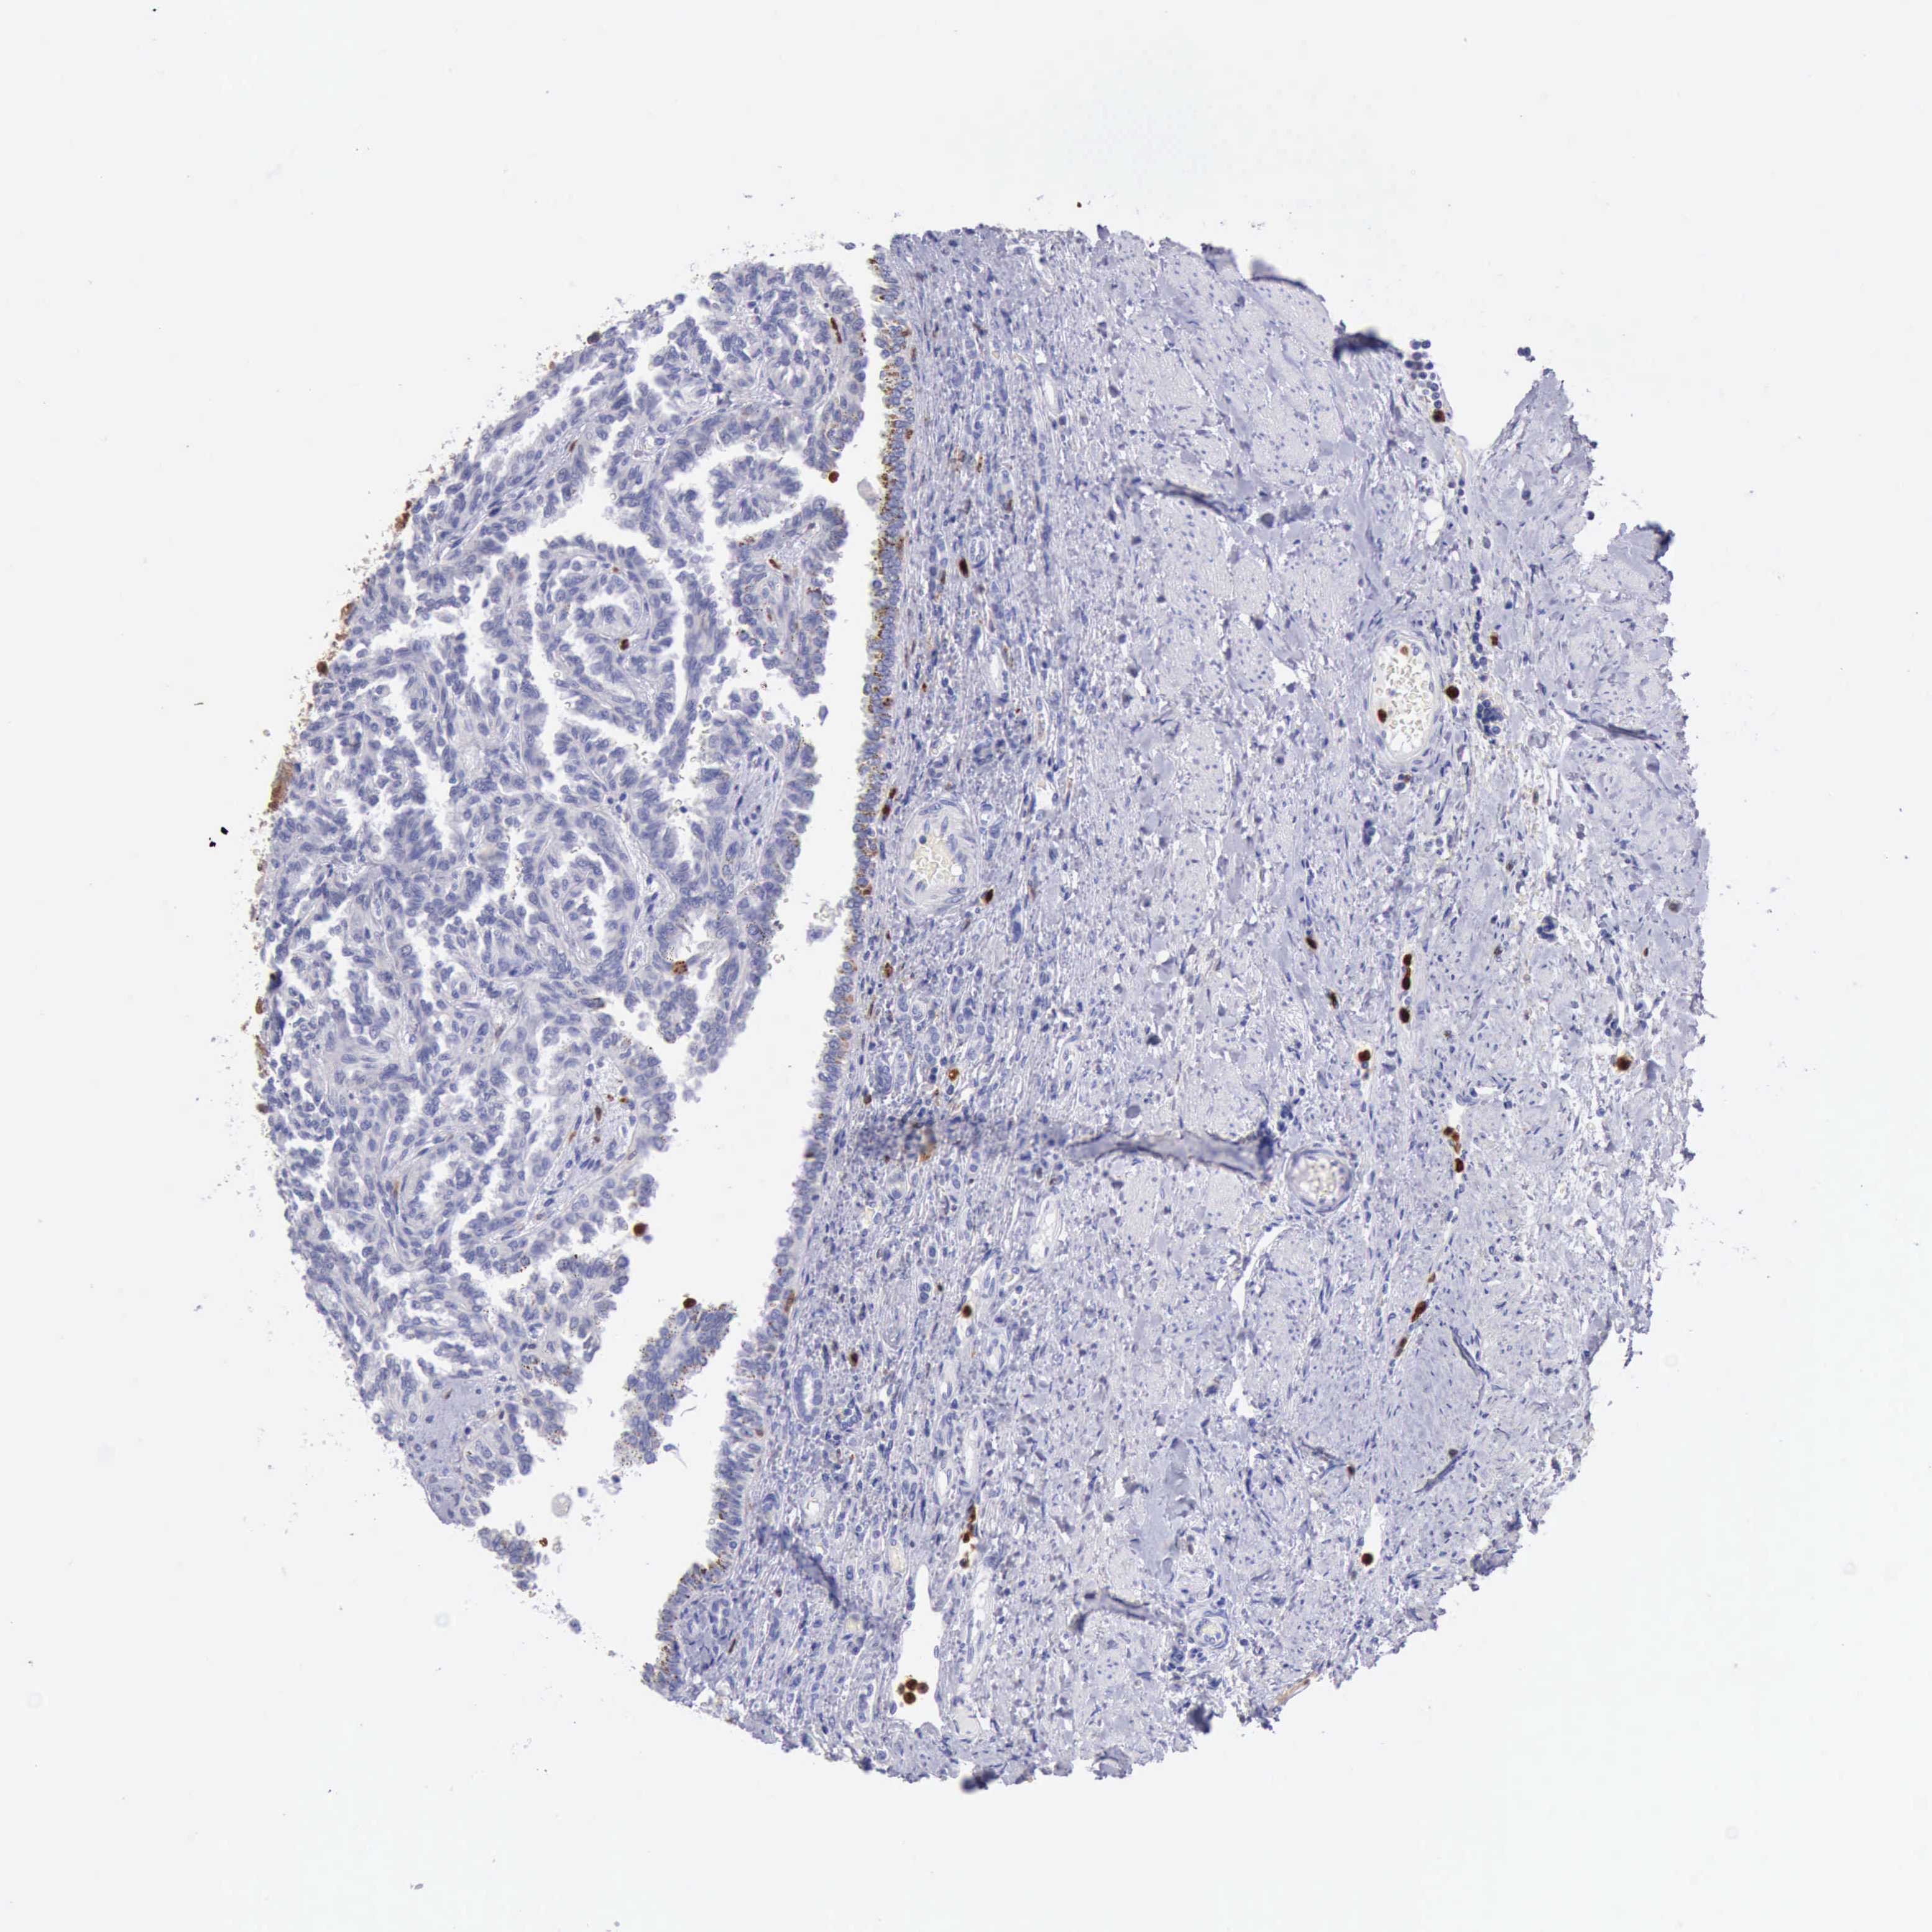

KIDNEY RENAL CLEAR CELL CARCINOMA (VALIDATION) - Interactive survival scatter ploti

The Survival Scatter plot shows the clinical status (i.e. dead or alive) for all individuals in the patient cohort, based on the same data that underlies the corresponding Kaplan-Meier plots. Patients that are alive at last time for follow-up are shown in blue and patients who have died during the study are shown in red.

The x-axis shows the expression levels (FPKM) of the investigated gene in the tumor tissue at the time of diagnosis. The y-axis shows the follow-up time after diagnosis (years). Both axes are complimented with kernel density curves demonstrating the data density over the axes. The top density plot shows the expression levels (FPKM) distribution among dead (red) and alive patients (blue). The right density plot shows the data density of the survived years of dead patients with high and low expression levels respectively, stratified using the cutoff indicated by the vertical dashed line through the Survival Scatter plot. This cutoff is automatically defined based on the FPKM cutoff that minimizes the p-score. The cutoff can be changed by dragging the vertical line or by entering a cutoff value in the square labeled "Current cut-off".

Under the Survival Scatter plot the p-score landscape (black curve; left axis) is shown together with dead median separation (red curve; right axis). Dead median separation is the difference in median mRNA expression between patients who have died with high and low expression, respectively. It is calculated as follows: median FPKM expression of dead patients with high expression - median FPKM expression of dead patients with low expression. This is intended to aid the user in visually exploring custom cutoffs and the associated p-scores and dead median separation.

Individual patient data is displayed and can be filtered by clicking on one or more of the category buttons on the top of the page. Categories describing expression level and patient information include: high, low, alive, dead, female, male and tumor stages. The scale of the x-axis can be toggled between linear and log-scale by clicking on the "x log" button. Mouse-over function shows TCGA ID, patient information and mRNA expression (FPKM) for each patient.

& Survival analysisi

Kaplan-Meier plots summarize results from analysis of correlation between mRNA expression level and patient survival. Patients were divided based on level of expression into one of the two groups "low" (under cut off) or "high" (over cut off). X-axis shows time for survival (years) and y-axis shows the probability of survival, where 1.0 corresponds to 100 percent.

CSTA is not prognostic in Kidney Renal Clear Cell Carcinoma (validation)

Best expression cut offi

Based on the FPKM value of each gene, patients were classified into two groups and association between prognosis (survival) and gene expression (FPKM) was examined. The best expression cut-off refers the FPKM value that yields maximal difference with regard to survival between the two groups at the lowest log-rank P-value. Best expression cut-off was selected based on survival analysis .

When clicking on this number, the vertical dashed line indicating cut-off, the interactive survival plot, and the Kaplan-Meier curve will be adjusted to show results based on the best expression cut-off.

: 19.04

P scorei

Log-rank P value for Kaplan-Meier plot showing results from analysis of correlation between mRNA expression level and patient survival.

N/A

Average pTPM 15.1

Number of samples 100